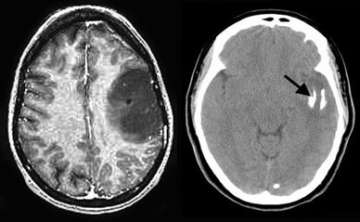

The MRI image (left) shows a large tumor in the left frontal lobe. The CT scan (right) shows that the tumor is partially calcified (arrow). The patient was successfully operated with awake speech mapping in the intra-operative MRI suite.

- Magnetic resonance imaging (MRI) is the preferred diagnostic tool, although computed tomography (CT) is important as well to document whether calcifications exist.

- Sometimes, oligodendroglioma are best removed with the aid of intra-operative MRI, allowing the most complete, safest surgery possible.